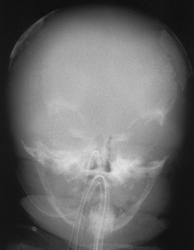

I тип проявляется уже при рождении тяжелыми деформациями скелета, что свидетельствует о развитии заболевания во внутриутробном периоде. Дети беспокойны, отмечаются рвота, анорексия, громкие вскрикивания, гипотония, дегидратация, лихорадочные состояния. Кости черепа и скелета мягкие, конечности сформированы, черепные швы расширены, большой родничок значительных размеров. Швы черепа закрываются рано.

Однако далеко не во всех случаях гипофосфатазии у плода ультразвуковое исследование скелета демонстрирует снижение эхогенности костей. J. Witts и соавт. описывают клиническое наблюдение, при котором в 17 нед беременности у плода отмечался незначительный подкожный отек и небольшое укорочение конечностей при их нормальной оссификации. Кариотип плода был нормальным, и беременность пролонгировали. В 31 нед укорочение костей стало выраженным, присоединилось многоводие. Для исключения ахондроплазии был сделан анализ на мутацию, характерную для этого заболевания. Ребенок родился в 35 нед и погиб сразу после родов. Только при рентгенологическом исследовании была выявлена сниженная минерализация черепа, платиспондилия позвоночника и истончение ребер, после чего было произведено гистологическое исследование костей и молекулярная диагностика, направленная на выявление мутаций, характерных для гипофосфатазии.